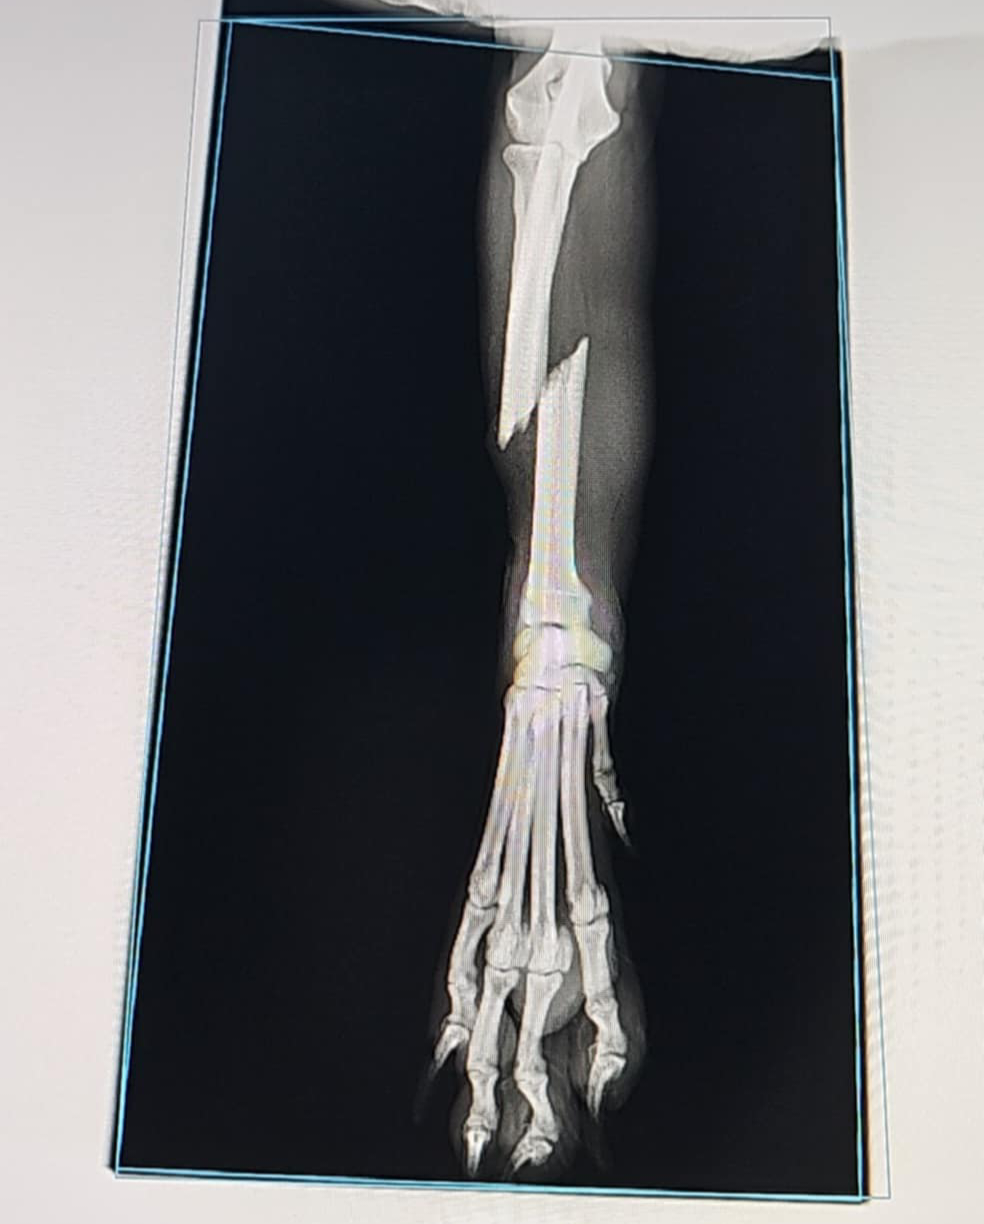

Nutusia Posted November 6, 2024 Author Posted November 6, 2024 Dnia 28.10.2024 o 15:05, Poker napisał: W swoich nieszczęściach Gi ma dużo szczęścia. Oby łapcia dobrze się zrosła i chłopak mógł śmigać. Dnia 30.10.2024 o 17:02, Nesiowata napisał: Jak chłopak po operacji? Dziewczyny kochane, dzięki że jesteście! Gi miewa się dużo lepiej. Operacja poszła zgodnie z planem, kość została zespolona za pomocą płytki i 7 śrub (brrr...), no i oczywiście naszego nieocenionego doktora! Wszystko goi się jak na psie Gigi już obciąża łapkę. Na spacerach chodzi na wszystkich 4 nogach, w domu jeszcze skacze na 3 jak wróbelek Ćwirek Chodzimy na coraz dłuższe spacery, oczywiście na smyczy, bo to dla niego najlepsza rehabilitacja. Kondycja rośnie z dnia na dzień, spacery się wydłużają. Smyczowe ograniczenie ruchu niestety aż do końca stycznia, ale damy radę. W najbliższy piątek zdjęcie szwów i opatrunku, więc będzie jeszcze wygodniej chodzić :) Poniżej foto zacerowanej łapki i rekonwalescenta na jego... domowym szpitalnym łożu 1 1 Quote

Nutusia Posted November 7, 2024 Author Posted November 7, 2024 Wstawiam informacyjnie zdjęcie RTG po naprawieniu łapki przez naszego Super Doktora Quote